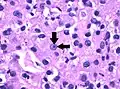

- Grade 3: Clearly visible nucleoli at magnification of 100 times

Grade 3: Arrows point at a clearly visible nucleolus.